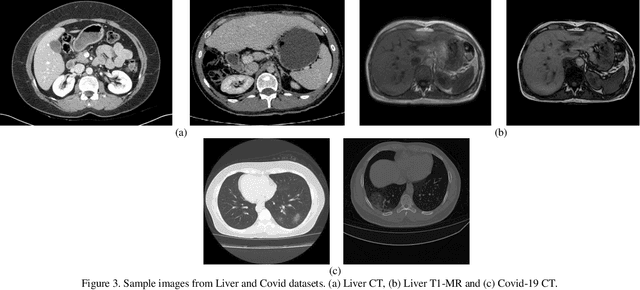

Abstract:Despite the widespread use of deep learning methods for semantic segmentation of images that are acquired from a single source, clinicians often use multi-domain data for a detailed analysis. For instance, CT and MRI have advantages over each other in terms of imaging quality, artifacts, and output characteristics that lead to differential diagnosis. The capacity of current segmentation techniques is only allow to work for an individual domain due to their differences. However, the models that are capable of working on all modalities are essentially needed for a complete solution. Furthermore, robustness is drastically affected by the number of samples in the training step, especially for deep learning models. Hence, there is a necessity that all available data regardless of data domain should be used for reliable methods. For this purpose, this manuscript aims to implement a novel model that can learn robust representations from cross-domain data by encapsulating distinct and shared patterns from different modalities. Precisely, covariate shift property is retained with structural modification and adversarial loss where sparse and rich representations are obtained. Hence, a single parameter set is used to perform cross-domain segmentation task. The superiority of the proposed method is that no information related to modalities are provided in either training or inference phase. The tests on CT and MRI liver data acquired in routine clinical workflows show that the proposed model outperforms all other baseline with a large margin. Experiments are also conducted on Covid-19 dataset that it consists of CT data where significant intra-class visual differences are observed. Similarly, the proposed method achieves the best performance.